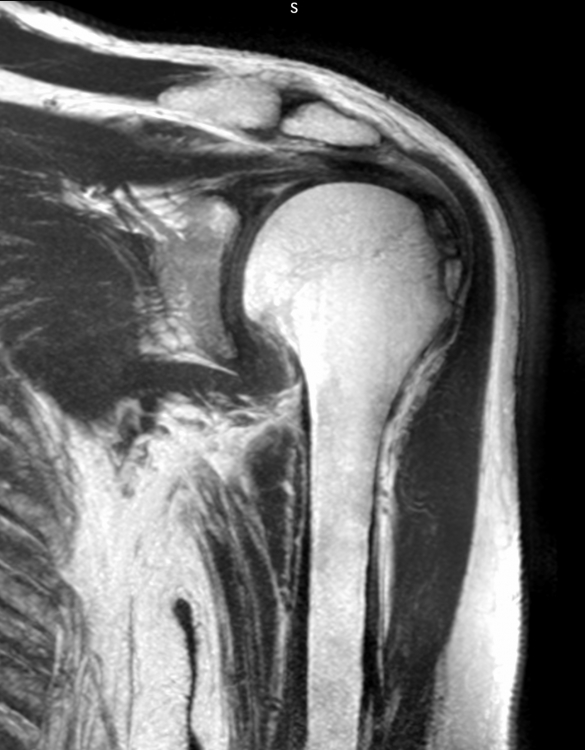

3. Röntgen am Unfalltag: --- MRT nach 6 Wochen (die Bilder habe ich selbst am PC gemacht - mein Arzt hat sie mir vorher gezeigt): --- Röntgen nach 12 Wochen: